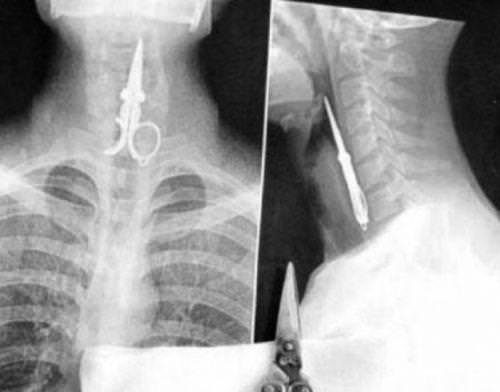

Röntgen filmlerinden "akıl almaz şeyler

Hastane koridorlarına düşenler bilir… Doktora görün, tahlilleri yaptır, röntgenleri çektir falan filan derken sayılmadan ömür gider. Gelin ki bu sefer ilginç şeyler çıkmış ki görün ağzımız açık kaldı…